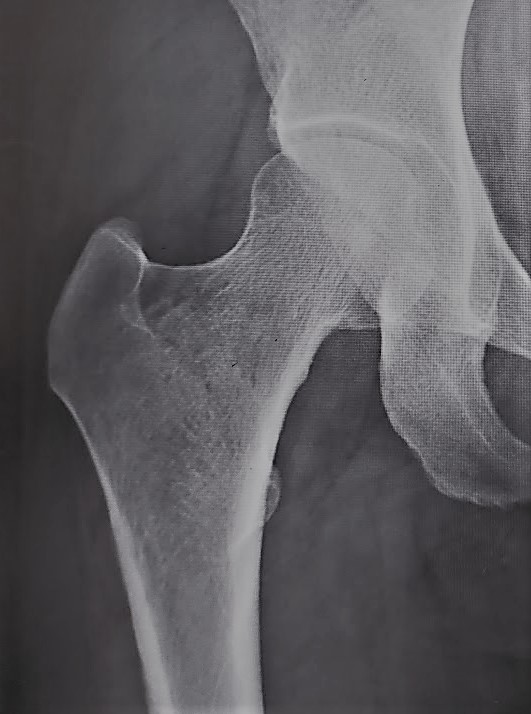

股関節の軟骨がすり減ることで痛みが生じる病気で圧倒的に女性に多いのが特徴です。骨の形の異常から二次的に発症するものが9割で、幼少期の股関節発育不全(臼蓋形成不全)のために骨盤側の受け皿の部分が浅いことが原因です。

〈臼蓋形成不全〉

臼蓋の被りが浅い

〈変形性股関節症〉

関節の隙間が消失